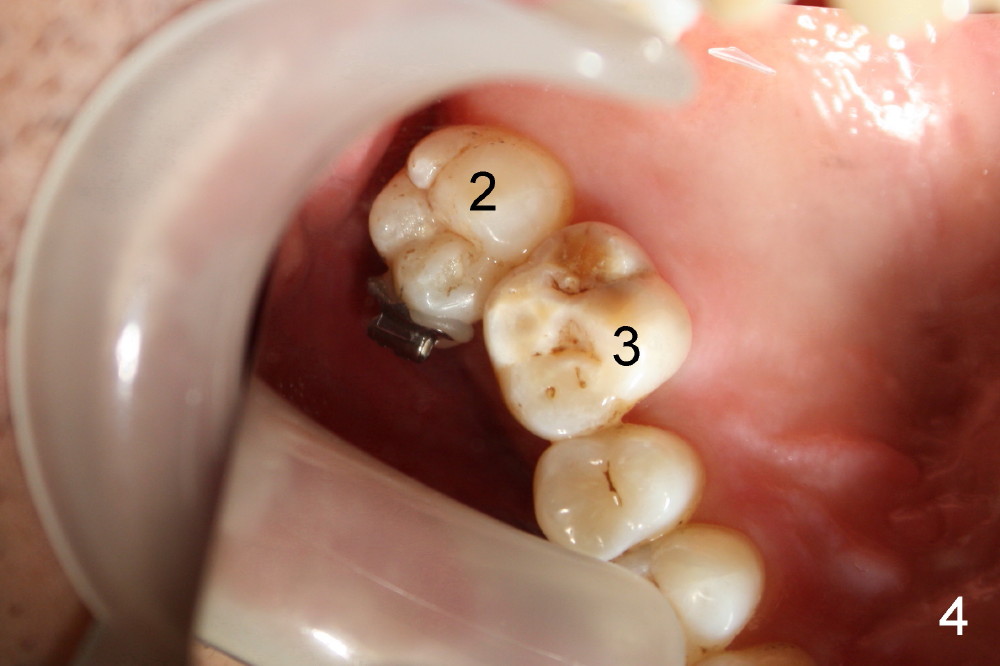

A 50-year-old man has lost the lower right 1st molar for several years (Fig.1: 30). The 2nd molar has shifted (arrow) and inclined (white line) mesially. It does not appear to occlude with the tooth #2 in this panoramic X-ray. It is planned to place an implant at the site of #30 and after osteointegration to use it as an anchorage to upright and distalize the tooth #31. Four and a half months after placement of a Tatum tapered implant (6x17 mm), a 5 mm 10 degree unipost ((short) abutment) is placed and prepared for temporary crown (Fig.2: A). Severe cross bite (overjet) is noted between the teeth #2 and 31. It is due to combination of the lingual inclination of the tooth #31 (Fig.3 (mirror view) arrow) and the buccal displacement of the tooth #2 (Fig.4 mirror image).